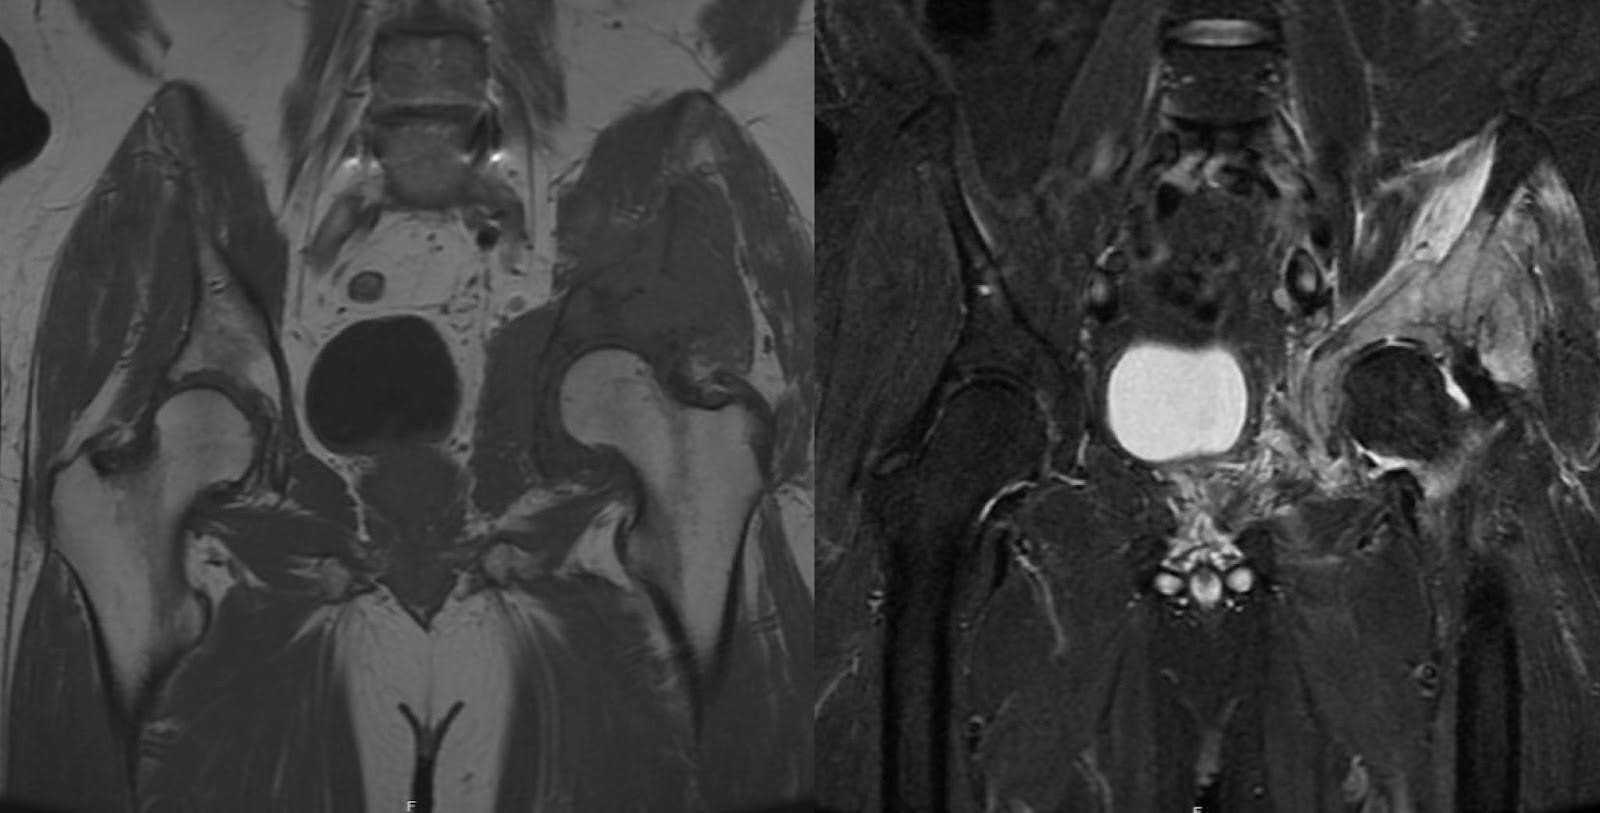

DLBCL is the most prevalent subtype of non-Hodgkin lymphoma, constituting approximately 30–40% of all cases.1 Diagnosis commonly occurs between the fifth and sixth decades of life. Its etiology is multifactorial and may involve genetic predispositions, immune dysregulation, as well as viral, environmental, and occupational exposures.2,3 It is marked by the proliferation of lymphopoietic cells, often originating within the bone, and has the potential to cause localized destruction of bony architecture, ultimately predisposing an individual to pathologic fractures.4 Clinically, DLBCL can present with skeletal pain secondary to bone destruction and destabilization. This pain may radiate, particularly when there is involvement of localized soft tissue components such as nerves, muscles, or vessels, depending on the lesion location. Systemic symptoms such as fever, night sweats, and weight loss can also be part of the constellation of symptoms.2,4,5 Imaging often reveals radiolucent bony destruction with soft tissue involvement, evident on plain film. Magnetic resonance imaging (MRI) typically shows relative hypotintensity on T1 sequences in the medullary canal, indicating bone marrow replacement. Additionally, T2 sequences commonly display hyperintensity within both intramedullary and extramedullary extension.6 Approximately four years before the pelvic stabilization surgery, the patient’s MRI revealed a T1 hypointense and T2 hyperintense lesion in the left acetabulum and innominate bone, consistent with a pathological process in these areas (Figure 3). The prominent soft tissue masses frequently observed at presentation for DLBCL can progress without systemic intervention. Standard treatment modalities for DLBCL involve chemotherapy and localized radiation therapy.7 DLBCL has a moderate to favorable prognosis, with 5-year survival rates ranging from 60–70% following first-line therapy.1

Figure 3. Preoperative MRI, taken approximately four years before pelvic stabilization surgery. MRI showed a T1 hypointense and T2 hyperintense lesion in the left acetabulum and innominate bone, suggestive of a pathological process.